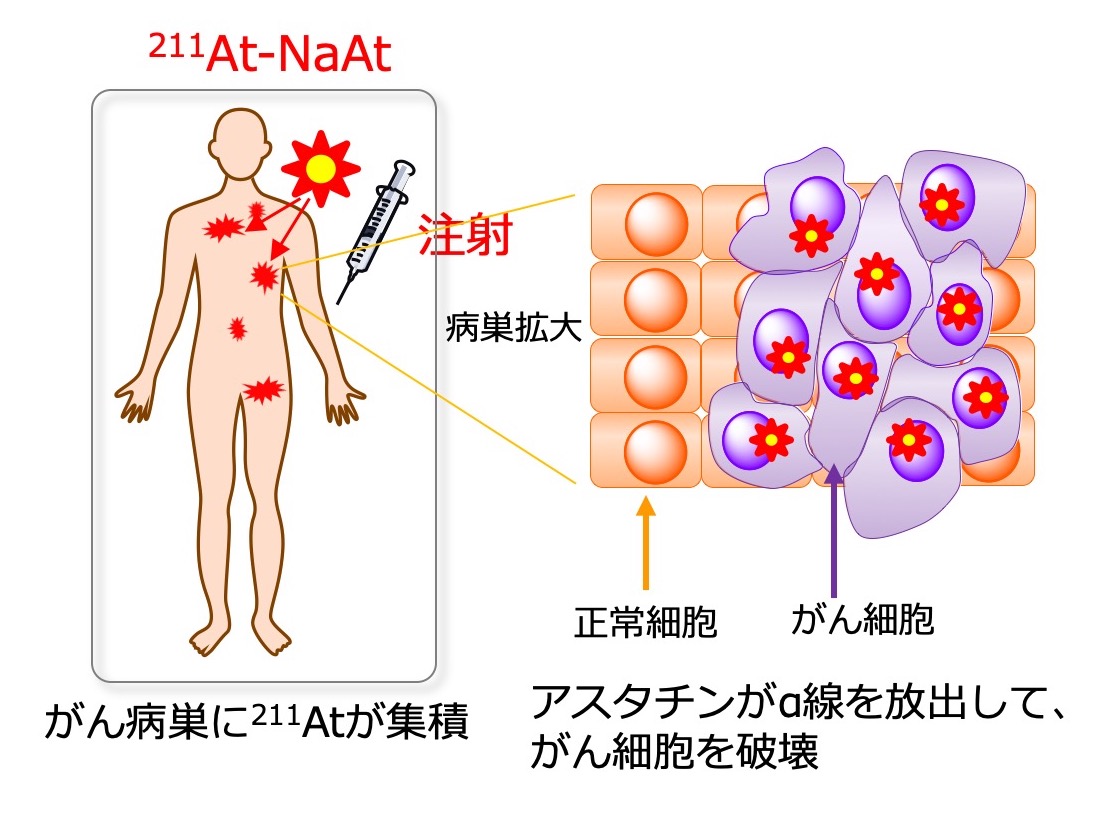

20443T, 難治性甲状腺がんに対する標的アルファ線核医学治療 (Targeted,

難治性甲状腺がんに対する標的アルファ線核医学治療 (Targeted, クッシング病(Cushing's disease) – 内分泌疾患 - 神戸きしだ,